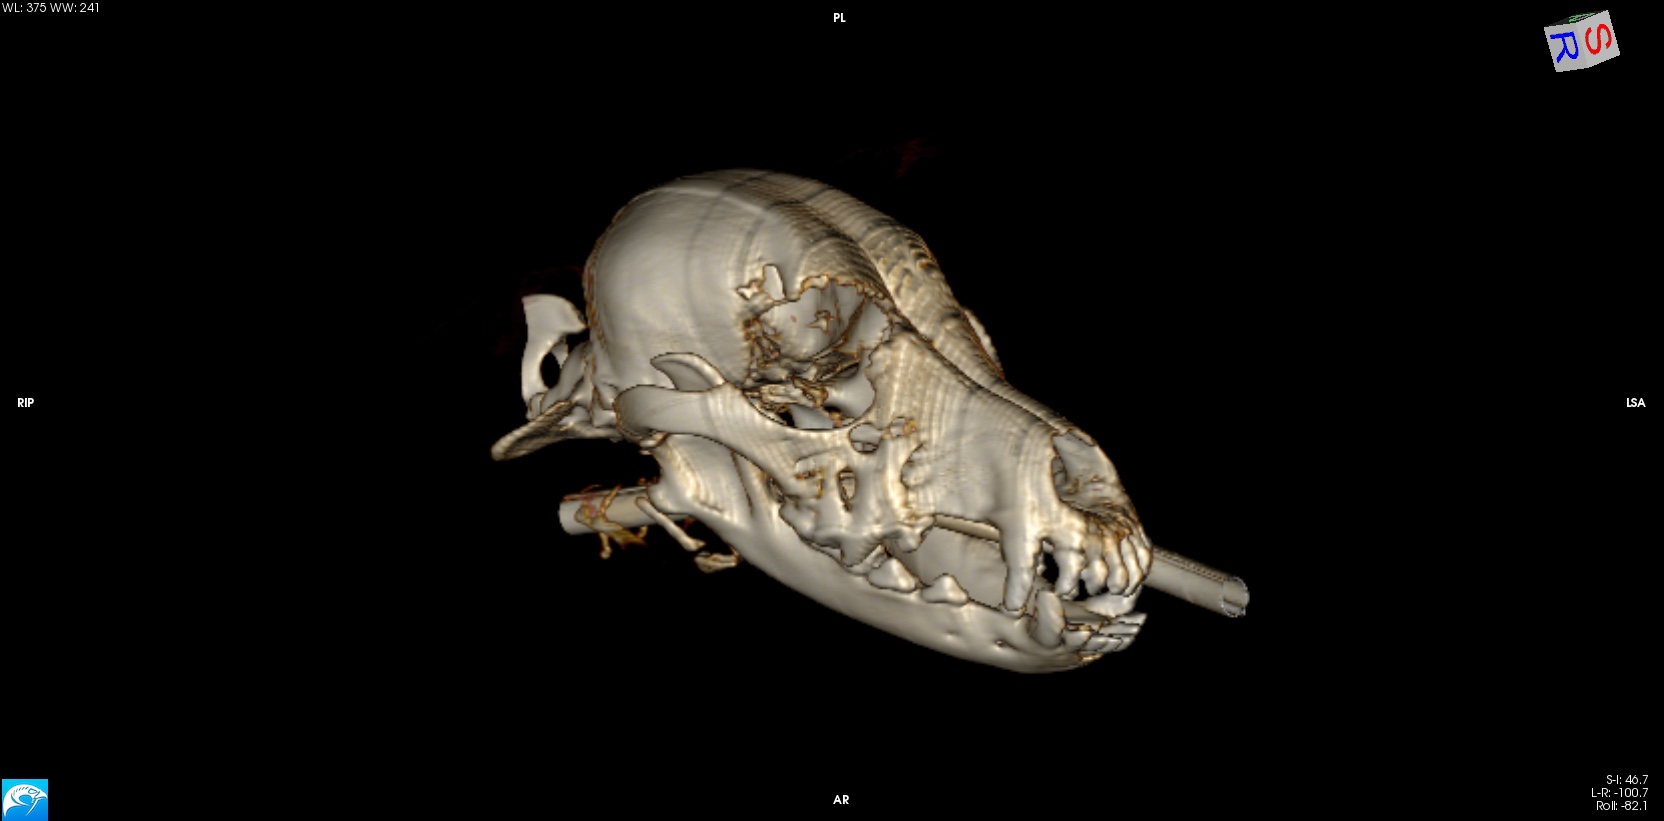

Outpatient Imaging